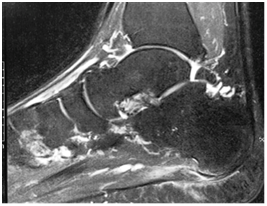

At the same time, imaging examinations were requested: Magnetic Resonance (MRI) of the foot 24 hours after the injury on the court 03/03/2017 Figure 2, 3 showing signs of acute traumatic rupture of the plantar fascia at calcaneus origin, with small plantar net collection without significant shrinkage. Central plantar fasciitis is associated with fusiform thickening of the fibers and degeneration area near the origin of the calcaneus, close to the area of traumatic rupture.

Figure 2 & 3 Magnetic Resonance of the foot performed with multiplanar cuts of 4.0mm showing signs of acute traumatic rupture of the plantar fascia at the calcaneus origin.